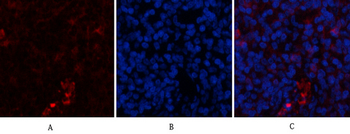

100 μlα-SMA Polyclonal Antibody [orb1411649]

IHC-P, WB

Human, Mouse, Rat

Rabbit

Polyclonal

Unconjugated